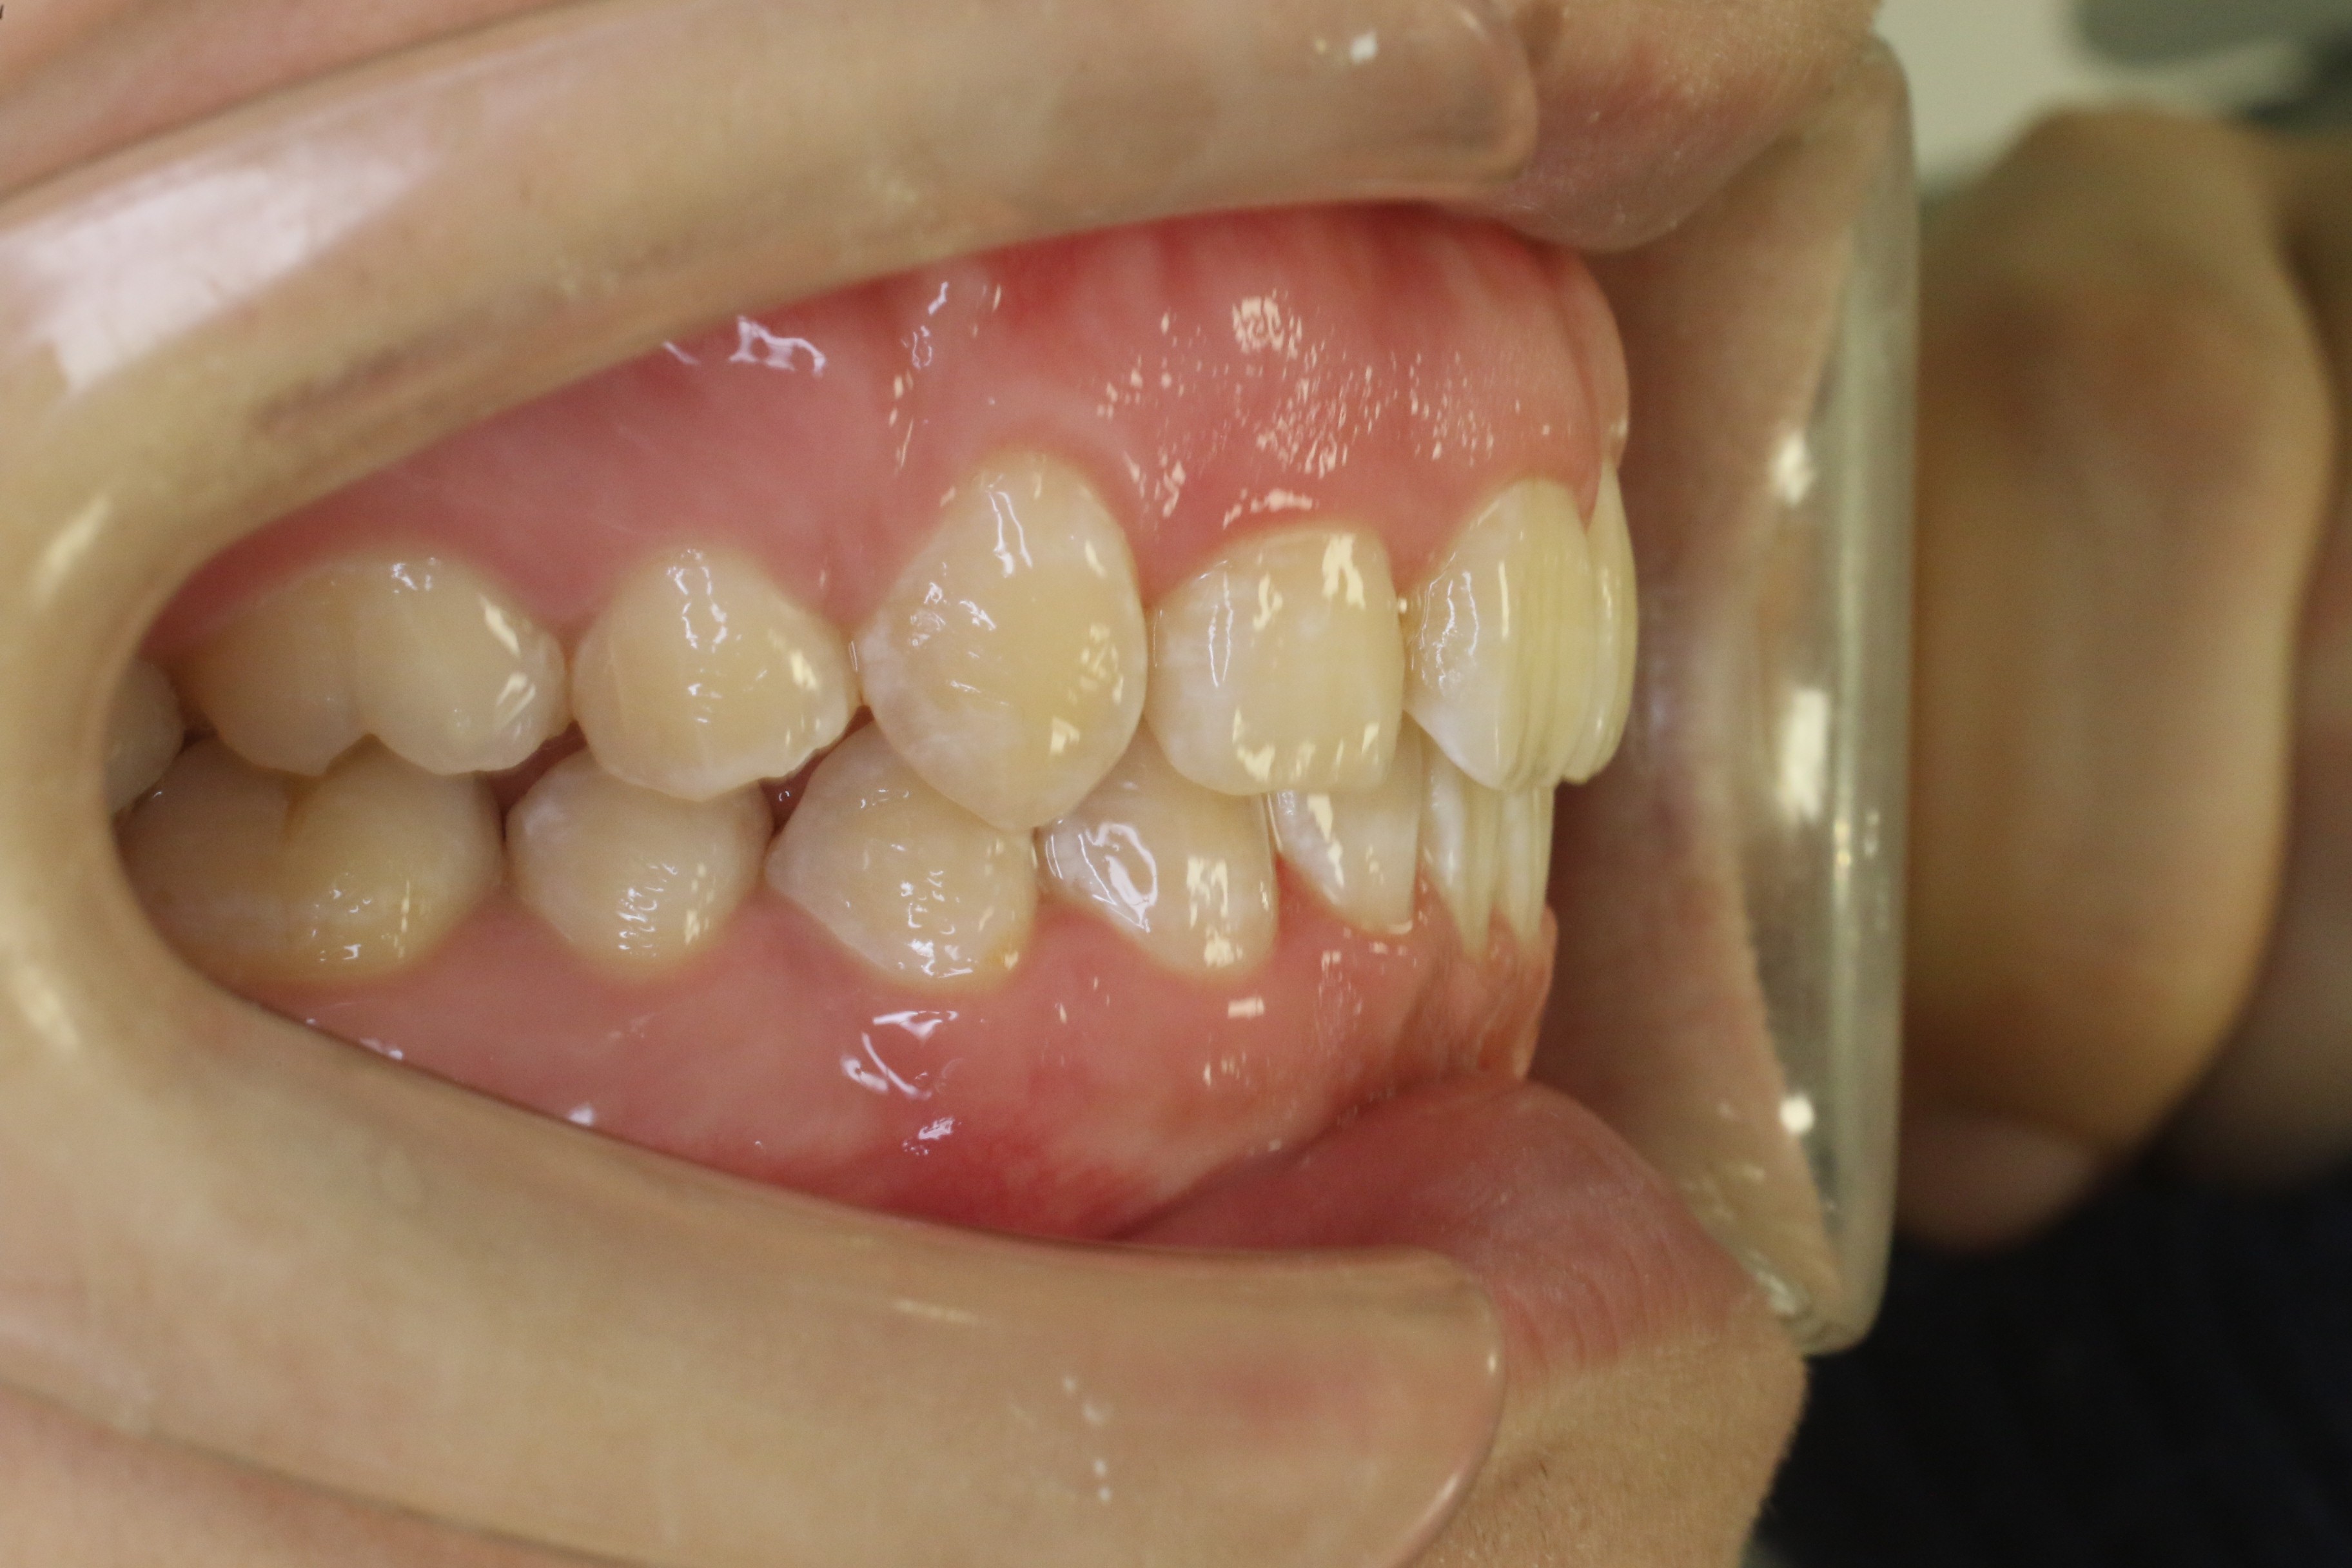

歯のデコボコを治したい

年齢層 30代

性別 男性

主訴 【主訴】歯のデコボコを治したい 【診断・症状】上下凸凹

治療費用 検査・診断:38,500-/裏側矯正治療:1,397,000-(※全て税込)

治療期間 約2年(26回)

抜歯 有(上4,4、下5,5)

矯正の装置 裏側矯正(舌側矯正)

副作用、リスク 歯肉退縮,歯根吸収,疼痛,咬合の違和感,装置の違和感,虫歯,歯肉炎

case8_デコボコ抜歯_before

Before